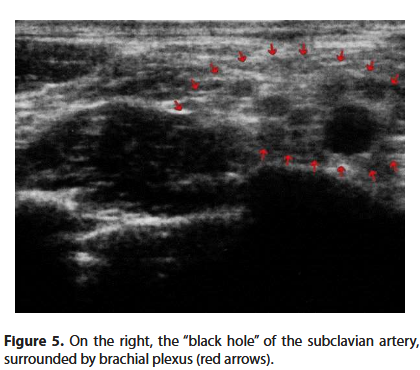

Now we can observe the pulsating black hole of the subclavian artery, surrounded by the transversely cut branches of the brachial plexus (Figure 5).